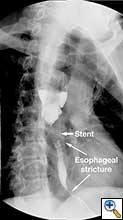

A 49 year old male presented to our institution with significant dysphagia and a 40 lb. weight loss secondary to a distal esophageal stricture. The patient had ingested lye 4 years previously and required partial gastrectomy, gastrojejunostomy, and partial colectomy at an outside institution at that time. His symptoms of dysphagia had progressively worsened despite repeated dilations and placement of an esophageal stent (Figure 1). Surgical reconstruction was therefore felt to be indicated. Preoperative computerized tomography angiogram did not clearly display the blood supply to the stomach, but did show that the colonic vasculature was adequate for use as a conduit if needed.

Figure 4. Postoperative barium swallow demonstrating free flow through the anastomosis with no residual stricture.

The patient had an uncomplicated course. His nasogastric tube was removed on postoperative day five. A water-soluble esophageal swallow study on postoperative day six demonstrated normal flow of contrast through the anastomosis and stomach into the jejunum, with no evidence of leak or obstruction (Figure 4). The patient was discharged to home on regular diet on postoperative day eleven. Pathologic analysis of the specimen revealed multiple strictures within the esophagus, to a diameter as narrow as 5 mm, and no evidence of malignancy. The patient had complete resolution of his dysphagia on 9 month follow-up and was returning to his baseline weight.